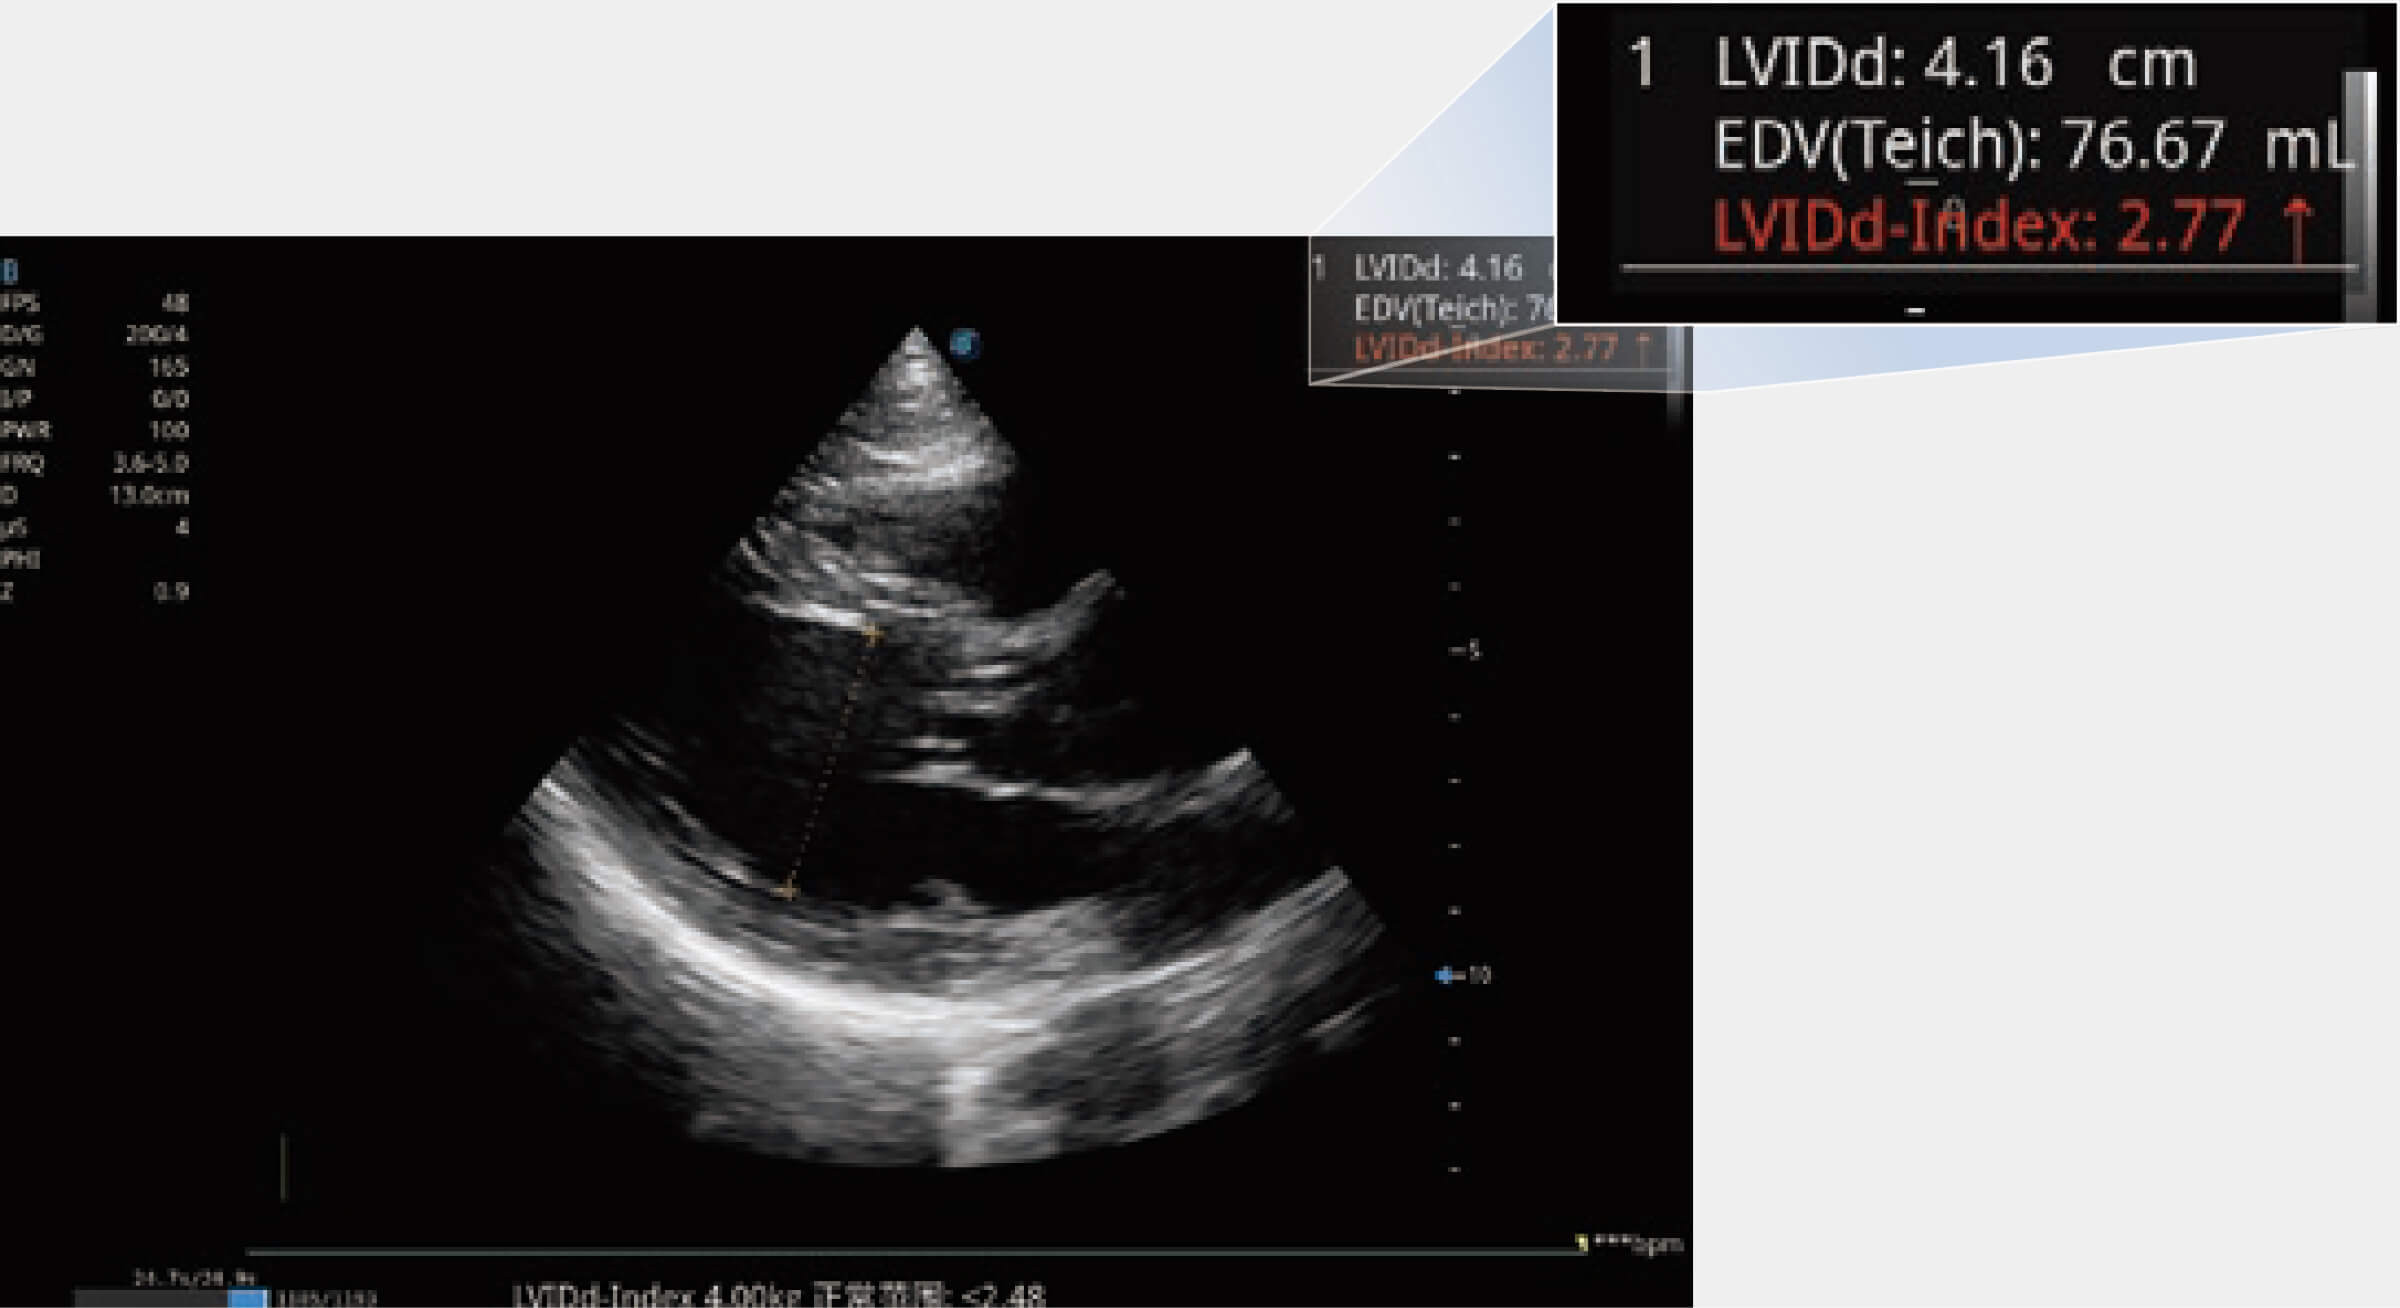

當(dāng)心臟測量結(jié)果超出正常范圍時,可實(shí)時預(yù)警提示動物醫(yī)生,減少疾病漏診概率。